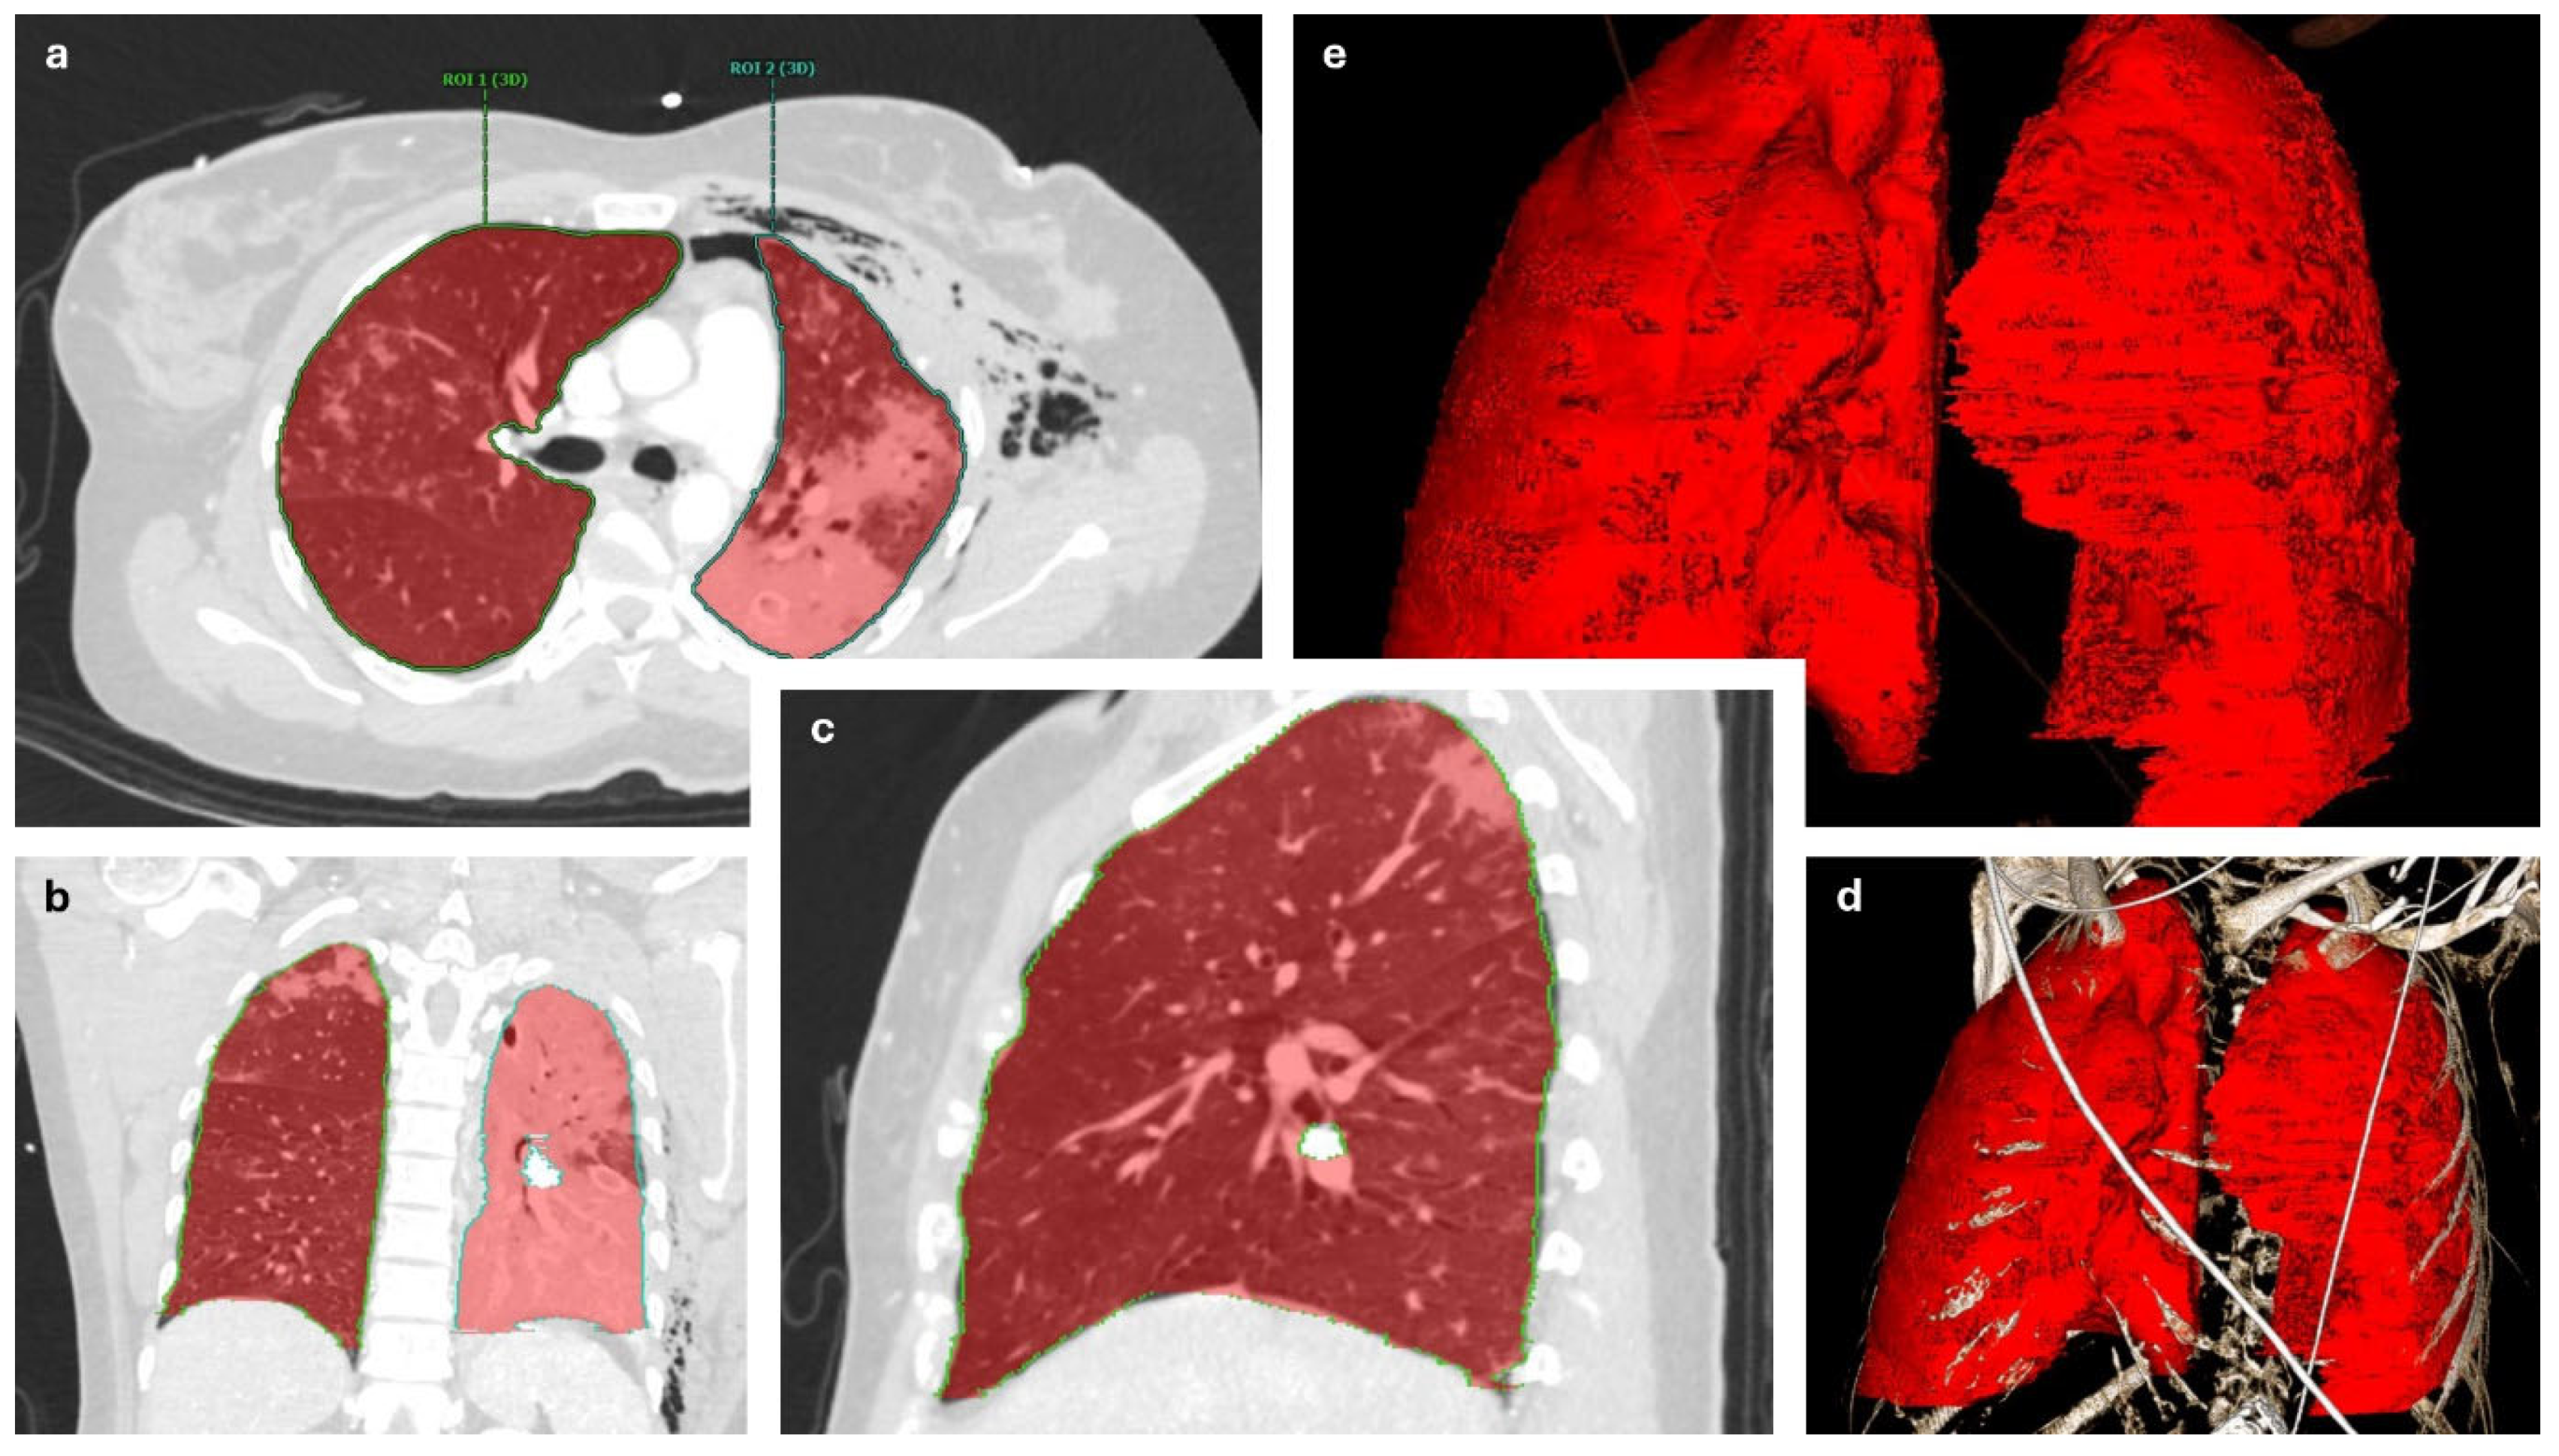

- Campbell, D.; Arnold, N.; Wake, E.; Grieve, J.; Provenzano, S.; Wullschleger, M.; Patel, B. Three-dimensional volume-rendered computed tomography application for follow-up fracture healing and volume measurements pre–surgical rib fixation and post–surgical rib fixation. J. Trauma Acute Care Surg. 2021, 91, 961–965. [Google Scholar] [CrossRef]